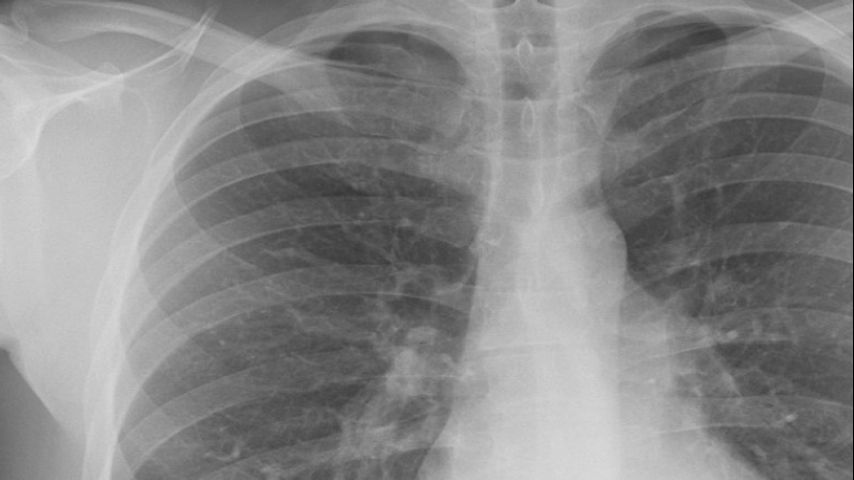

Is There A Lung Cancer Awareness Month - 8th International Conference on Clinical and Medical Case ... : Testing, clinical trial enrollment challenges recognized during lung cancer awareness month.. Lung cancer awareness month is observed annually in november. This year, the american cancer society estimates about 221,200 new cases, and about 158,040 deaths from lung cancer. Lung cancer awareness month the american lung association's lung force initiative is uniting women and their loved ones across the country to stand together against lung cancer, the #1 cancer killer of women and men in the u.s., with your support, we can raise critical awareness about lung cancer and turn the tide against this disease. Though we commonly think of lung cancer as a disease that affects tobacco smokers, it can affect anyone. In the united states, lung cancer is the second most common cancer in both men and women.

Lung cancer has a survival rate of 15% and is currently the leading cause of cancer death.

November is lung cancer awareness month, a time when lung cancer survivors, families, caregivers, advocates and fundraisers focus their efforts like a laser to increase awareness of this disease. Pleomorphic, carcinoid tumor, salivary gland carcinoma, and unclassified carcinoma. During this observance, we raise awareness about what lung cancer is, how you get cancer, how to lower your risk, and how important screening is for those at high risk. Lung cancer awareness month the american lung association's lung force initiative is uniting women and their loved ones across the country to stand together against lung cancer, the #1 cancer killer of women and men in the u.s., with your support, we can raise critical awareness about lung cancer and turn the tide against this disease. This november join lcfa in our efforts to raise awareness of the need for more research and better community awareness of this disease. In the united states, lung cancer is the second most common cancer in both men and women. Each year, more people die of lung cancer than of colon, breast, and prostate cancers combined. It's important to know the symptoms of lung cancer as although lung cancer occurs mostly in people aged 60 and over, it can affect people of any age. This year, the american cancer society estimates about 221,200 new cases, and about 158,040 deaths from lung cancer. November is pancreatic cancer, lung cancer, stomach cancer and carcinoid cancer awareness month. November is also a month during which we honor caregivers. It is the second most common cancer among both men and women in the united states. The goal is to encourage everyone to take a few minutes to review what is known so far about lung cancer, and possibly learn something new.